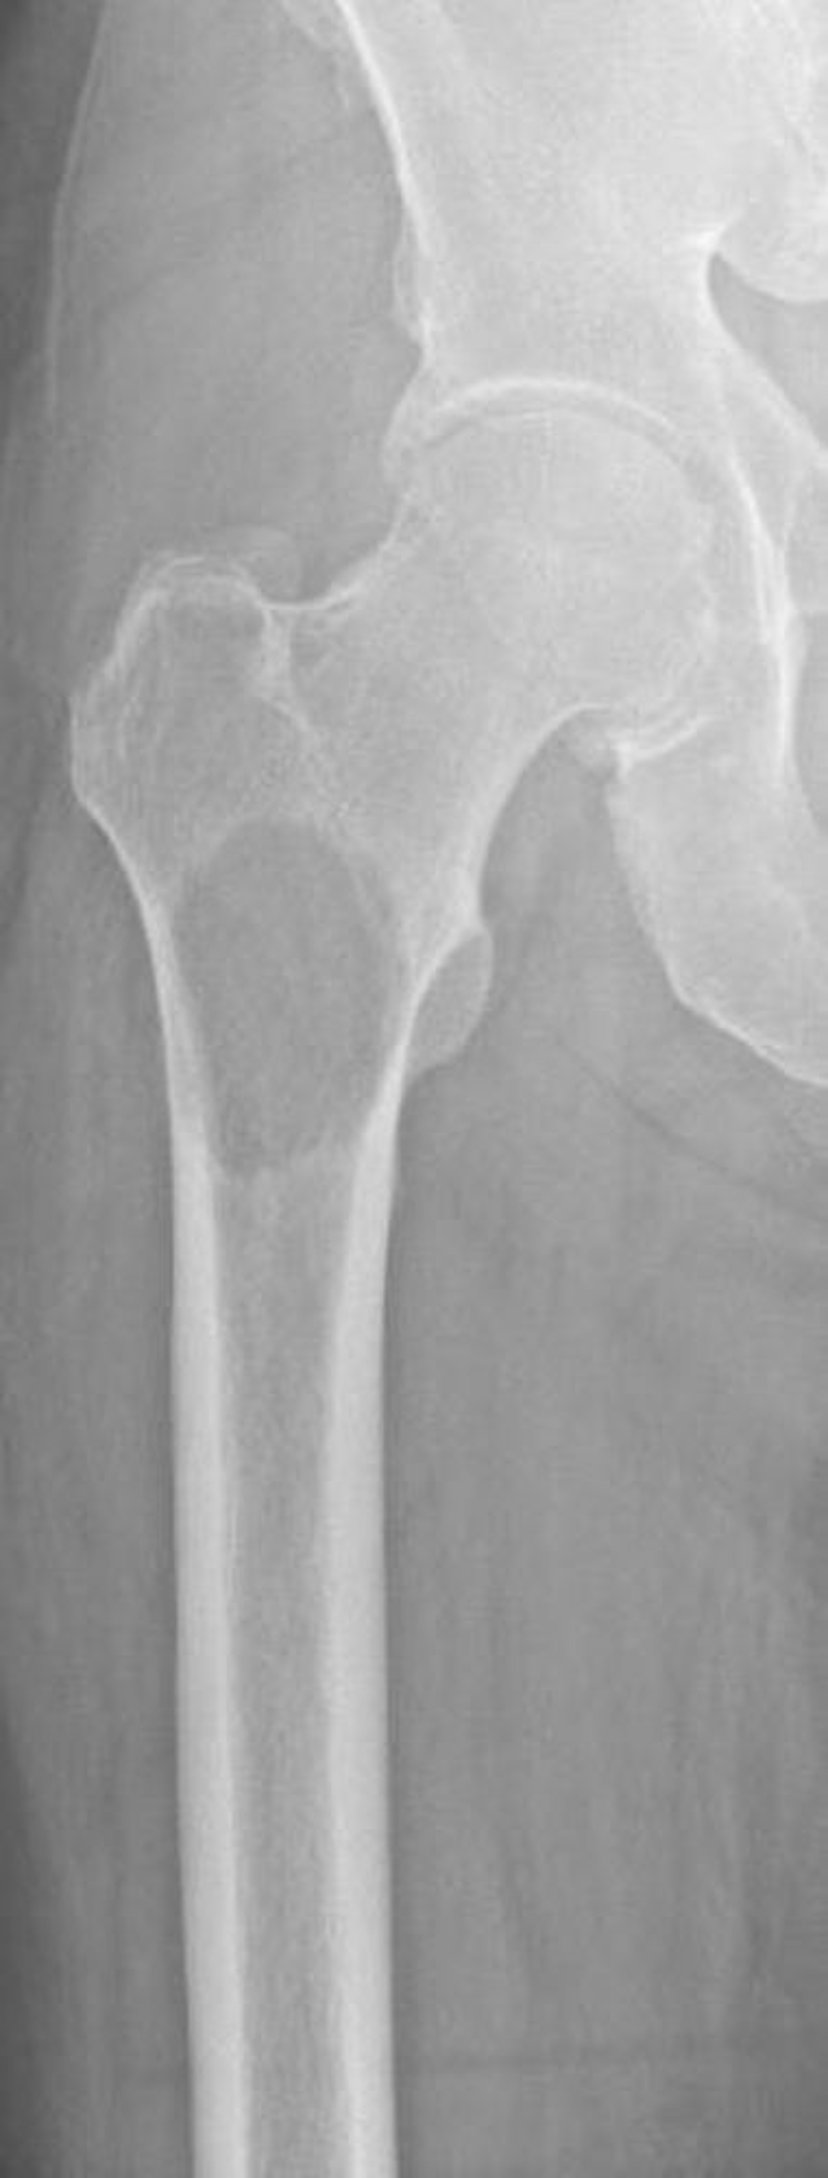

Литические метастазы в проксимальной части бедренной кости

Это изображение показывает костную деструкцию в проксимальном отделе бедренной кости вследствие метастазов, вторичных по отношению к почечно-клеточному раку. Локализация и степень деструкции кости делают риск перелома чрезвычайно высоким (неизбежный перелом).